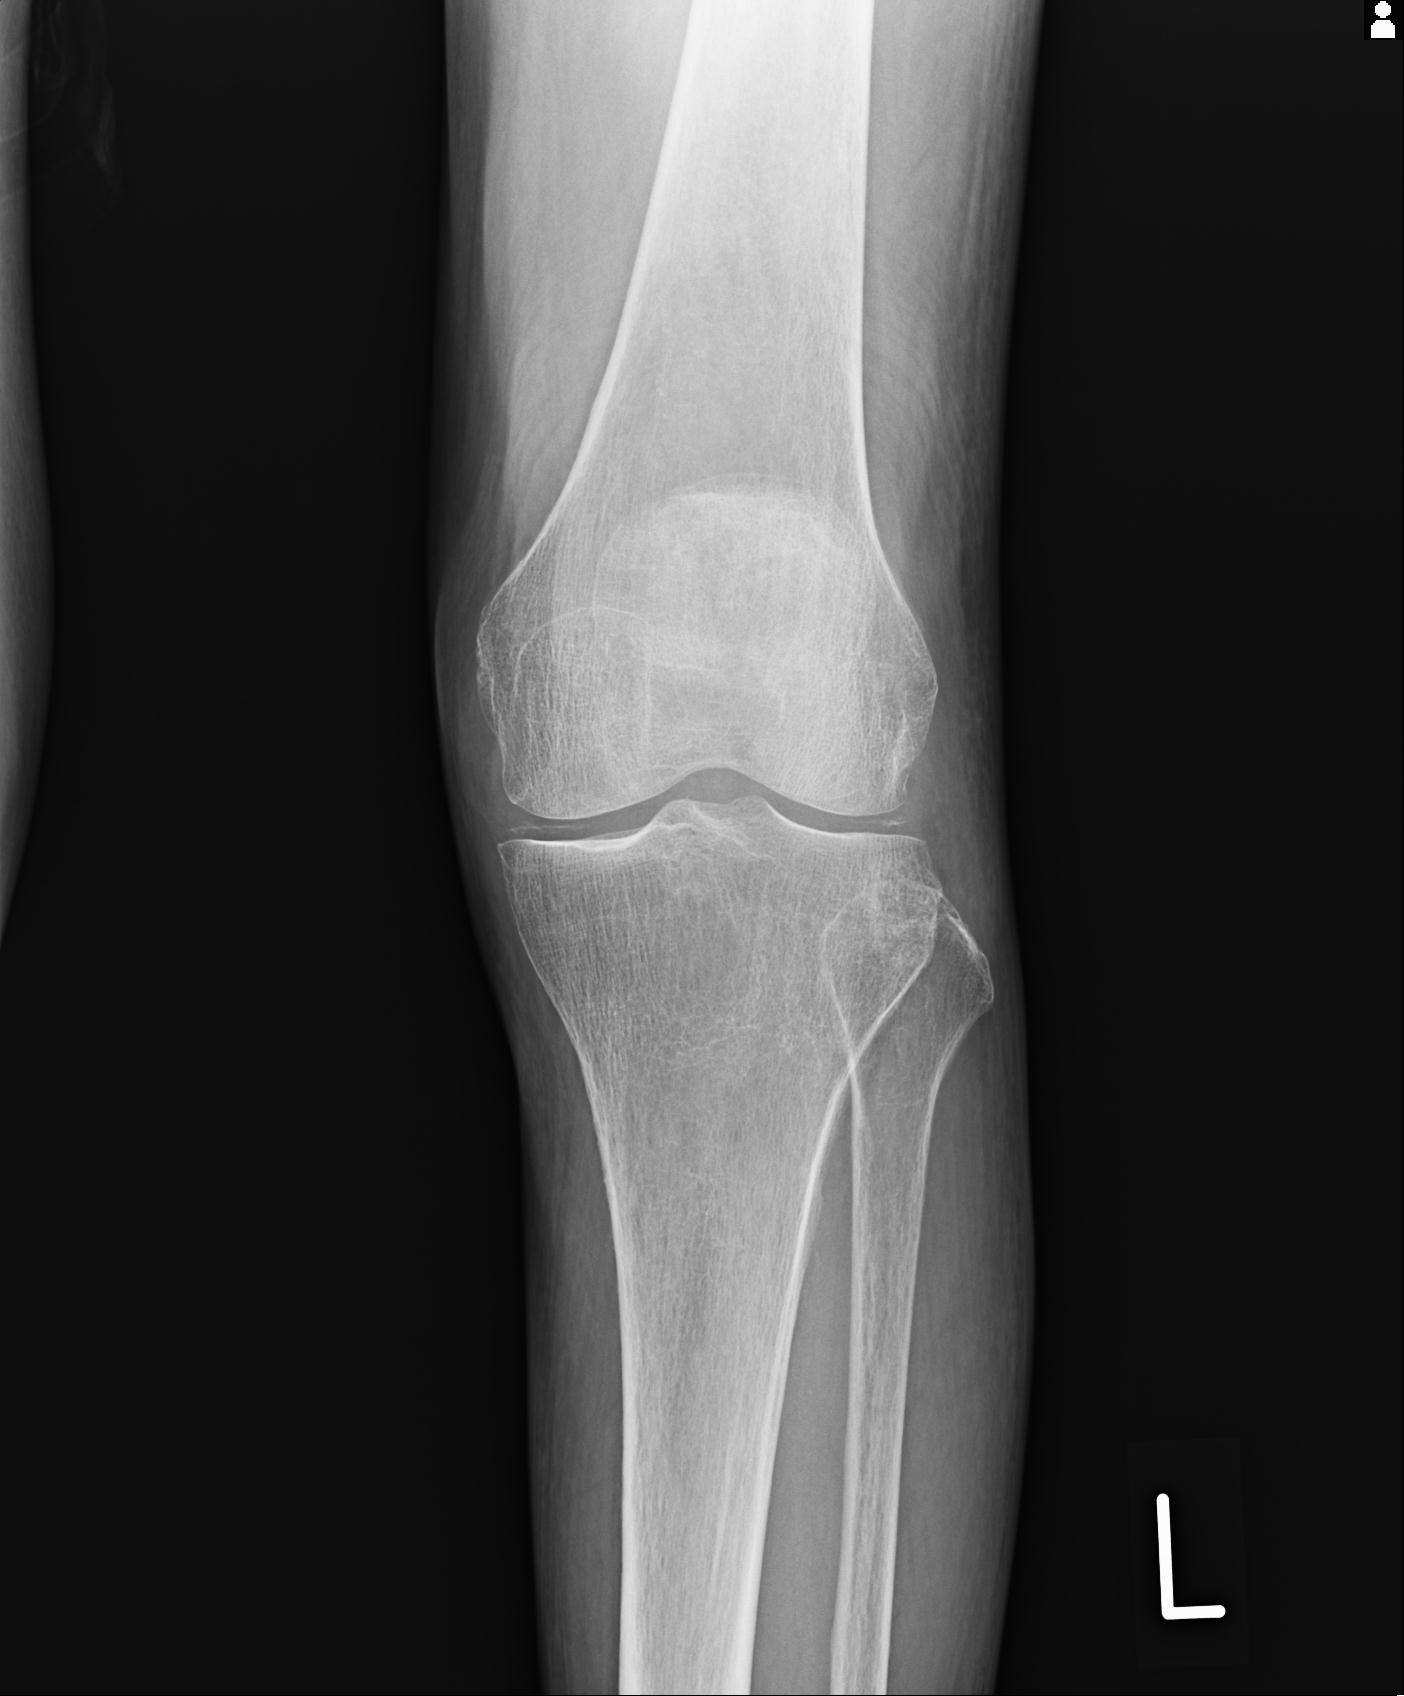

100612 11/25 1/20 右膝 2R 84歳女性 右TKA